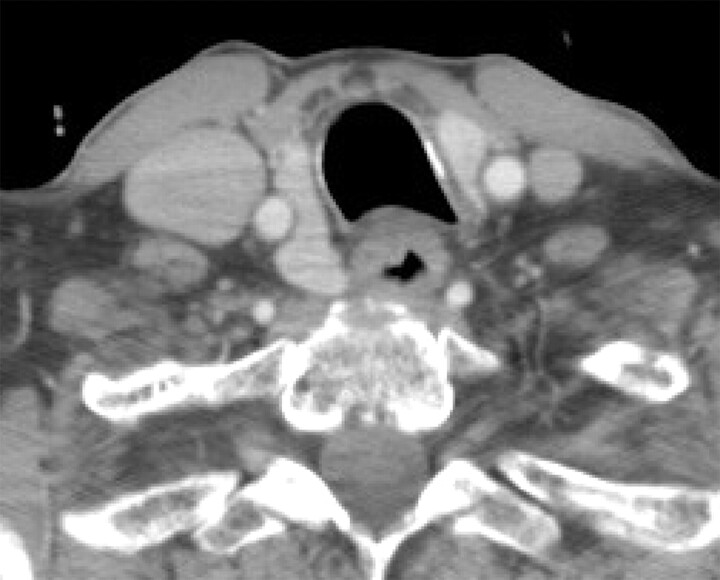

Patient A, our index case, is a 40-year-old woman with recurrent ovarian cancer who presented with symptoms of hoarseness and was found to have a possible metastatic neck lesion. On imaging, the lesion appeared contiguous with the posterior aspect of the right thyroid lobe. On 1 neck CT, it had artifactually lowered attenuation due to streak artifact from the shoulders, but on another CT, it had similar attenuation and enhancement (Fig 4). The right common carotid artery was situated on the lateral aspect of the thyroid and the questionable metastatic lesion. The appearance was stable compared with a remote pulmonary embolism chest CT from 2006 (Fig 6), but due to the initial radiologic concern, a sonography-guided fine-needle aspiration of the nodular area was performed, with pathology read as indeterminate.

Fig 4.

Patient A, with known ovarian carcinoma recurrence in the abdomen, presented with a few weeks' history of voice hoarseness and was noted to have a nodular area posterior to the right thyroid lobe. There was clinical concern for a metastasis or exophytic thyroid nodule.

Patient A's pulmonary embolism chest CT from 2006 shows similar appearance of the questionable thyroid lesion.

Due to ongoing clinical concern by the referring head and neck surgeon, a percutaneous core needle biopsy was performed at our institution (Fig 5), yielding normal thyroid tissue.